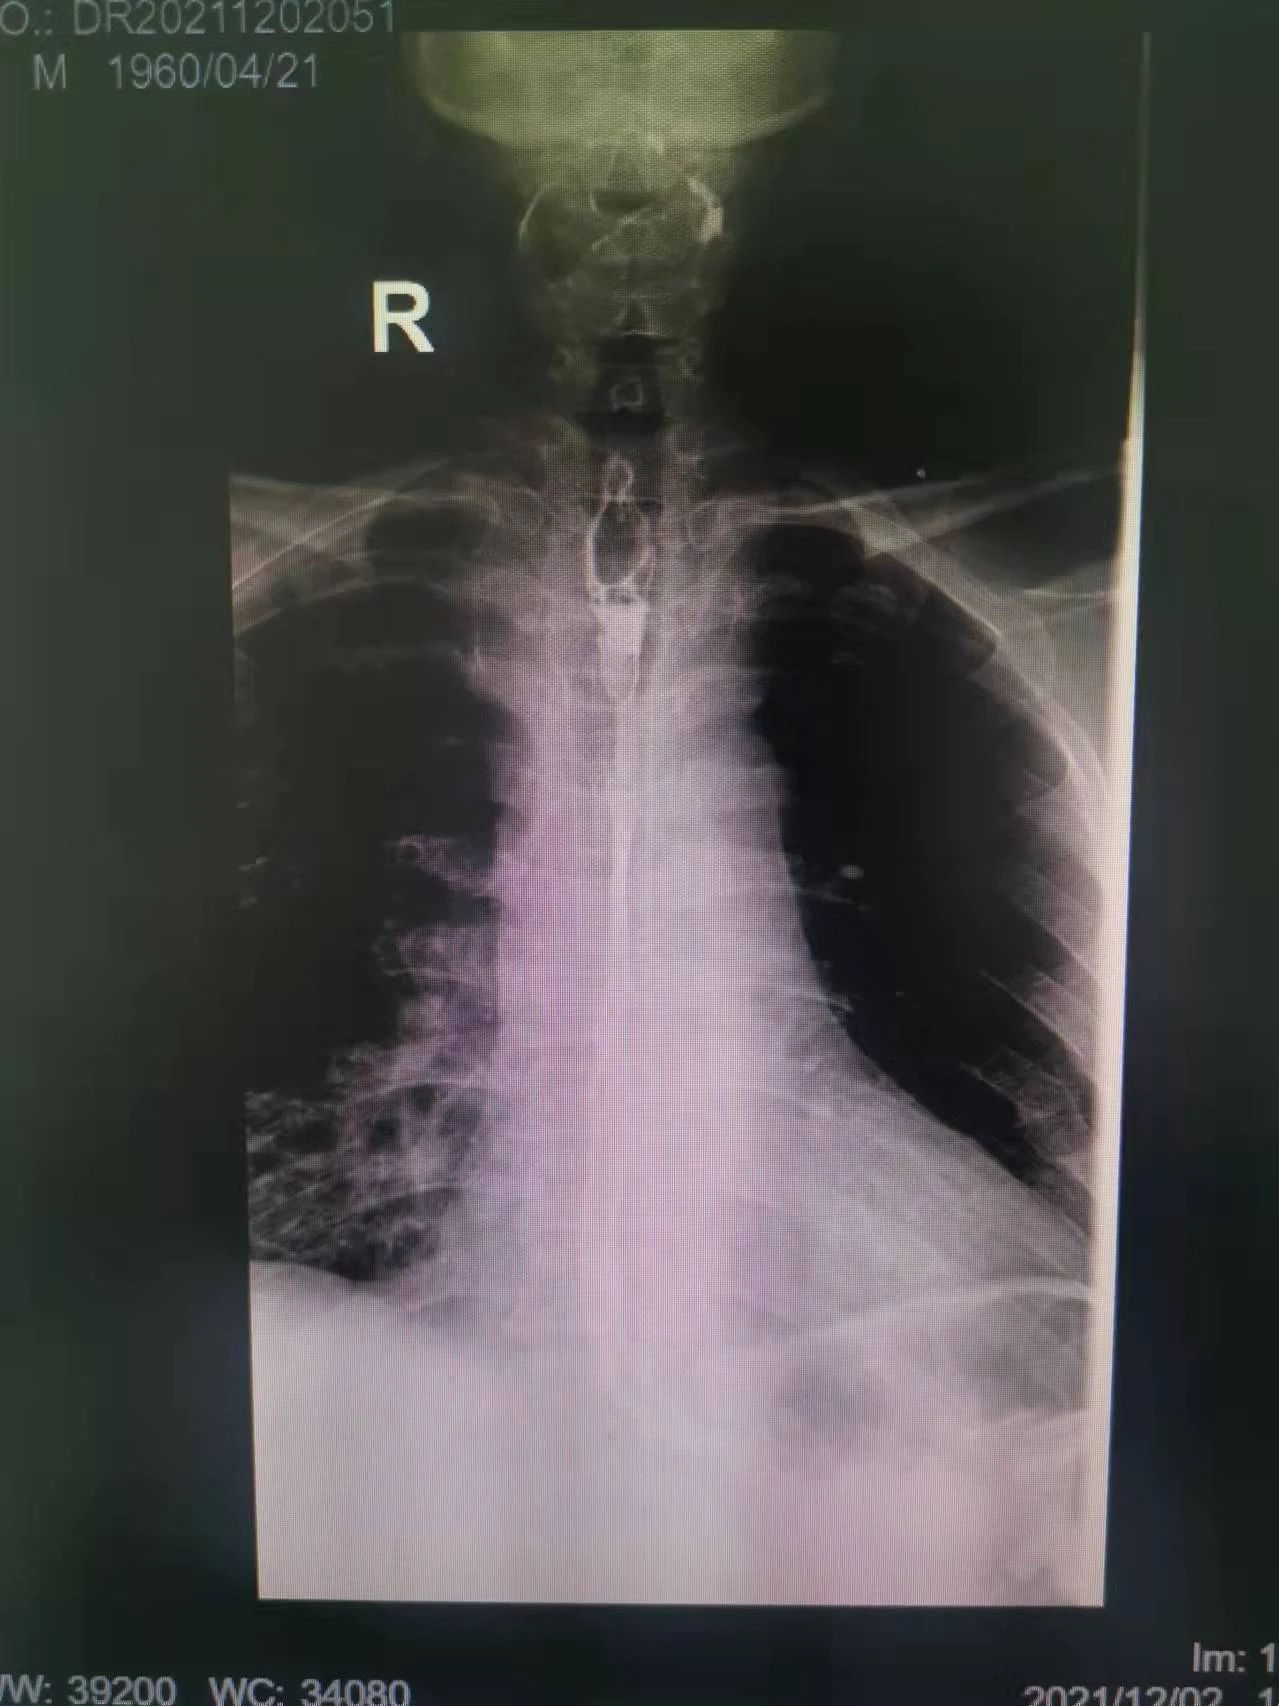

在這種情況下,我院介入二科侯主任決定通過介入治療中的食管支架植入來幫助患者實現(xiàn)這個愿望。手術(shù)當(dāng)日,侯主任在機(jī)器的幫助下,將一根細(xì)細(xì)的導(dǎo)絲穿過腫瘤到達(dá)付大爺胃部,然后再沿著導(dǎo)絲,把壓縮好的支架放在腫瘤里面。通過后撤導(dǎo)管,把壓縮的支架打開,支架把腫瘤撐開,讓食管不再堵塞。有了支架的支撐,付大爺就可以自由地吃東西了,哪怕食管和氣管有溝通,因為支架覆蓋了腫瘤,通道堵住了,吃的東西也不會吸到肺內(nèi)造成感染。這時痛痛快快地吃上一頓,也不再是奢望!

手術(shù)很順利,付大爺也在術(shù)后第2天喝到了自己日思夜想的清水,露出了久違的笑容。從某種意義上講,介入食管支架置入術(shù)的成功實施,付大爺不能進(jìn)食的病已經(jīng)“治好”了,雖然從生理角度來說,付大爺可以通過終生使用腸內(nèi)營養(yǎng)來維持生存,但我們所做的是致力于給予患者更好的生存體驗,或者說是尊嚴(yán)。銘記并保持一名醫(yī)者的初心,我們要做的正如那句著名的墓志銘所說:有時去治愈,常常去幫助,總是去安慰。